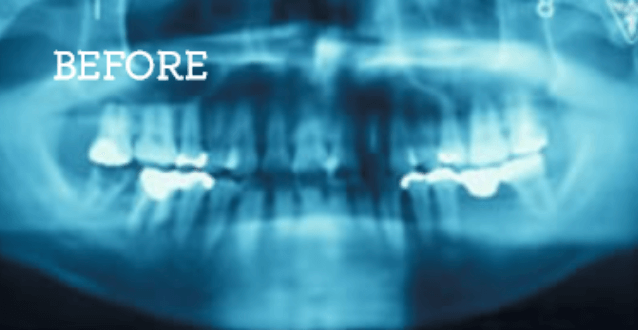

症例

お困りごとを参考に、治療のbefore・afterが確認できます。治療過程や期間、費用などを参考にご覧ください。